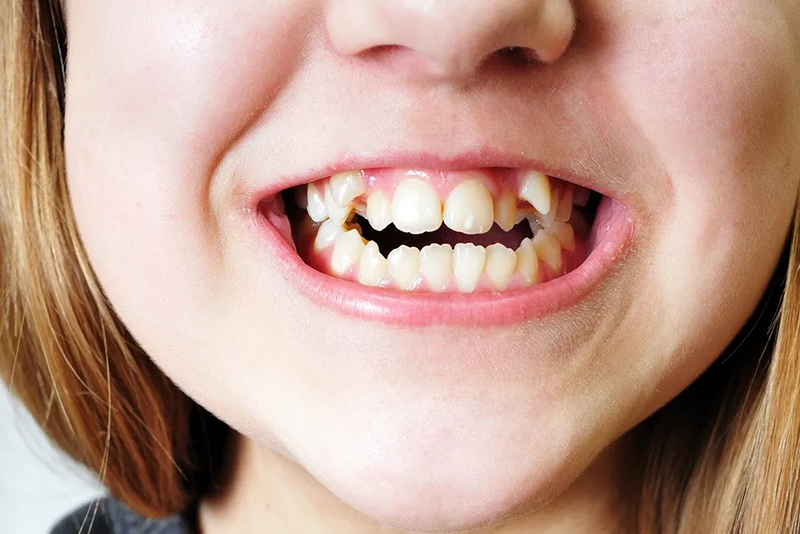

Răng mọc khấp khểnh là tình trạng mọc răng một cách xô đẩy và chen chúc trên cung hàm. Điều này góp phần làm gương mặt trở nên kém thẩm mỹ, ảnh hưởng đến chức năng ăn nhai, khả năng phát âm, đồng thời việc chăm sóc vệ sinh răng miệng cũng trở nên khó khăn, từ đó gây nên các vấn đề viêm nướu, sâu răng, lâu dài có thể dẫn đến mất răng.